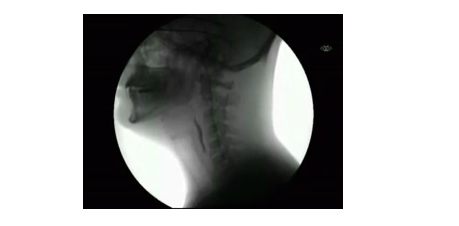

Żucie gumy i połykanie w promieniach rentgena (wideo)

X-ray of chewing and swallowing food